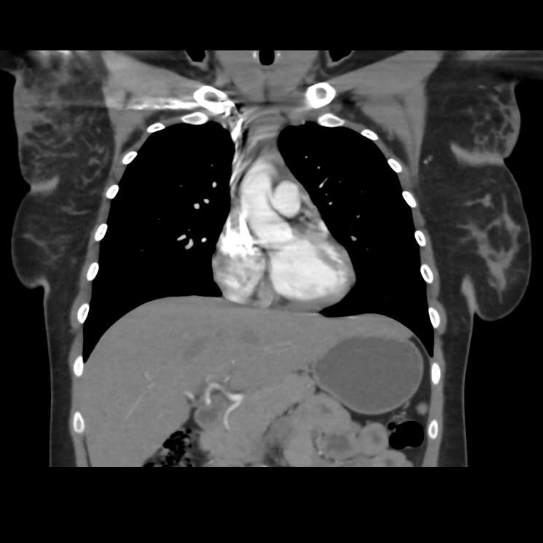

腋下空間(圖片的錐狀區域)是所有腋下淋巴結的主要分布區,其中最深層、靠近腋頂處與內側壁交界的深層脂肪,是前哨淋巴結常見的位置。

人體腋下由外而內分為:皮膚、皮下脂肪層、淺筋膜以及深層的腋窩空間。

具有重要免疫功能的淋巴結群,特別是前哨淋巴結,通常位於淺筋膜之下的深層脂肪墊,並與支配上肢的動靜脈血管及神經結構相伴而行,這個層次是乳癌手術與腫瘤外科會進入的區域,並不是美容手術該碰觸的範圍。